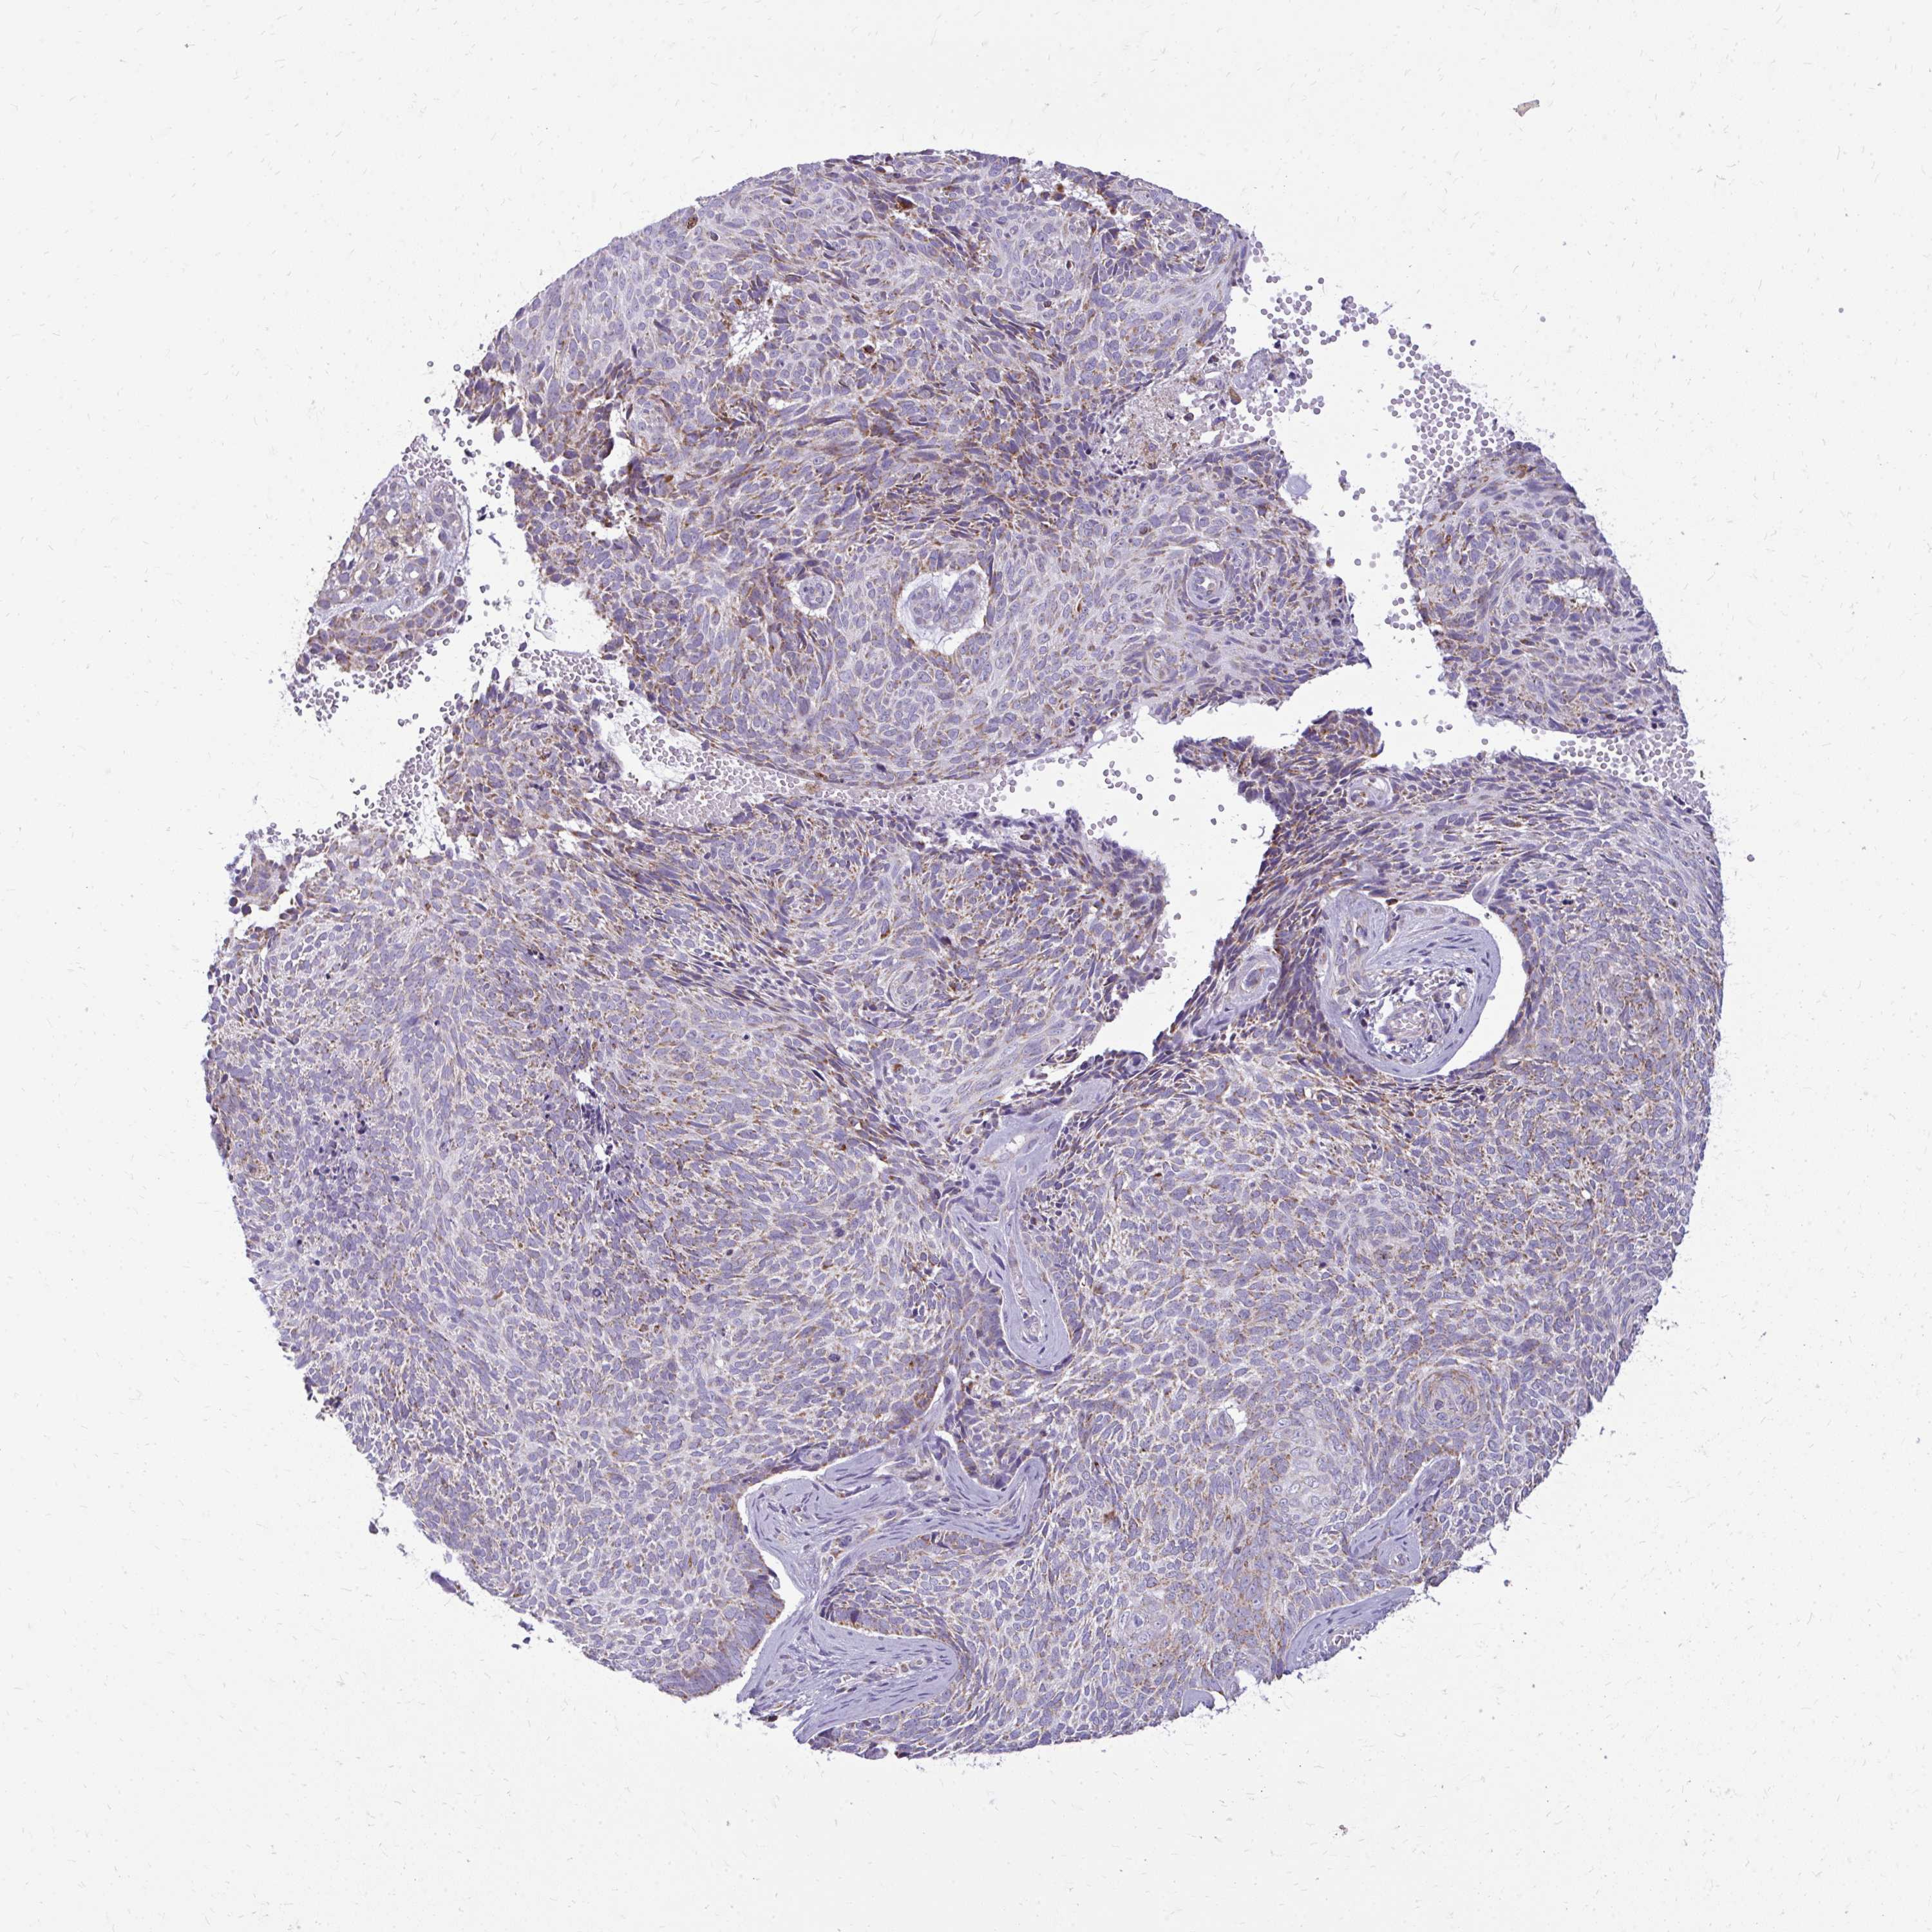

SKIN CANCER - Protein expressioni

A mouse-over function shows sample information and annotation data. Click on an image to view it in a full screen mode. Samples can be filtered based on level of antibody staining by selecting one or several of the following categories: high, medium, low and not detected. The assay and annotation is described here.

Each image is clickable and will lead to virtual microscopy that enables deeper exploration of all samples and also displays staining intensity scores, fraction scores and subcellular localization as well as patient and tissue information for each sample.

Antibody HPA055380

Basal cell carcinoma